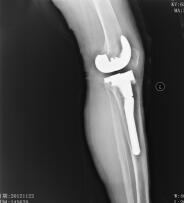

入院后完善各项检查,择期行左膝关节表面假体置换术,术中外侧平台骨质缺损较大,应用10mm垫片,加用胫骨延长柄(图3)。复查X线片(图4)示假体安装准确,左下肢力线良好,切口甲级愈合。术后1天指导患者行功能锻炼,逐渐下床负重行走,出院时左膝关节可屈曲110°。术后1年复查,左膝关节活动度0°~120°,稳定性良好,无疼痛不适,患者自我评价良好。

图4 术后正侧位X线片